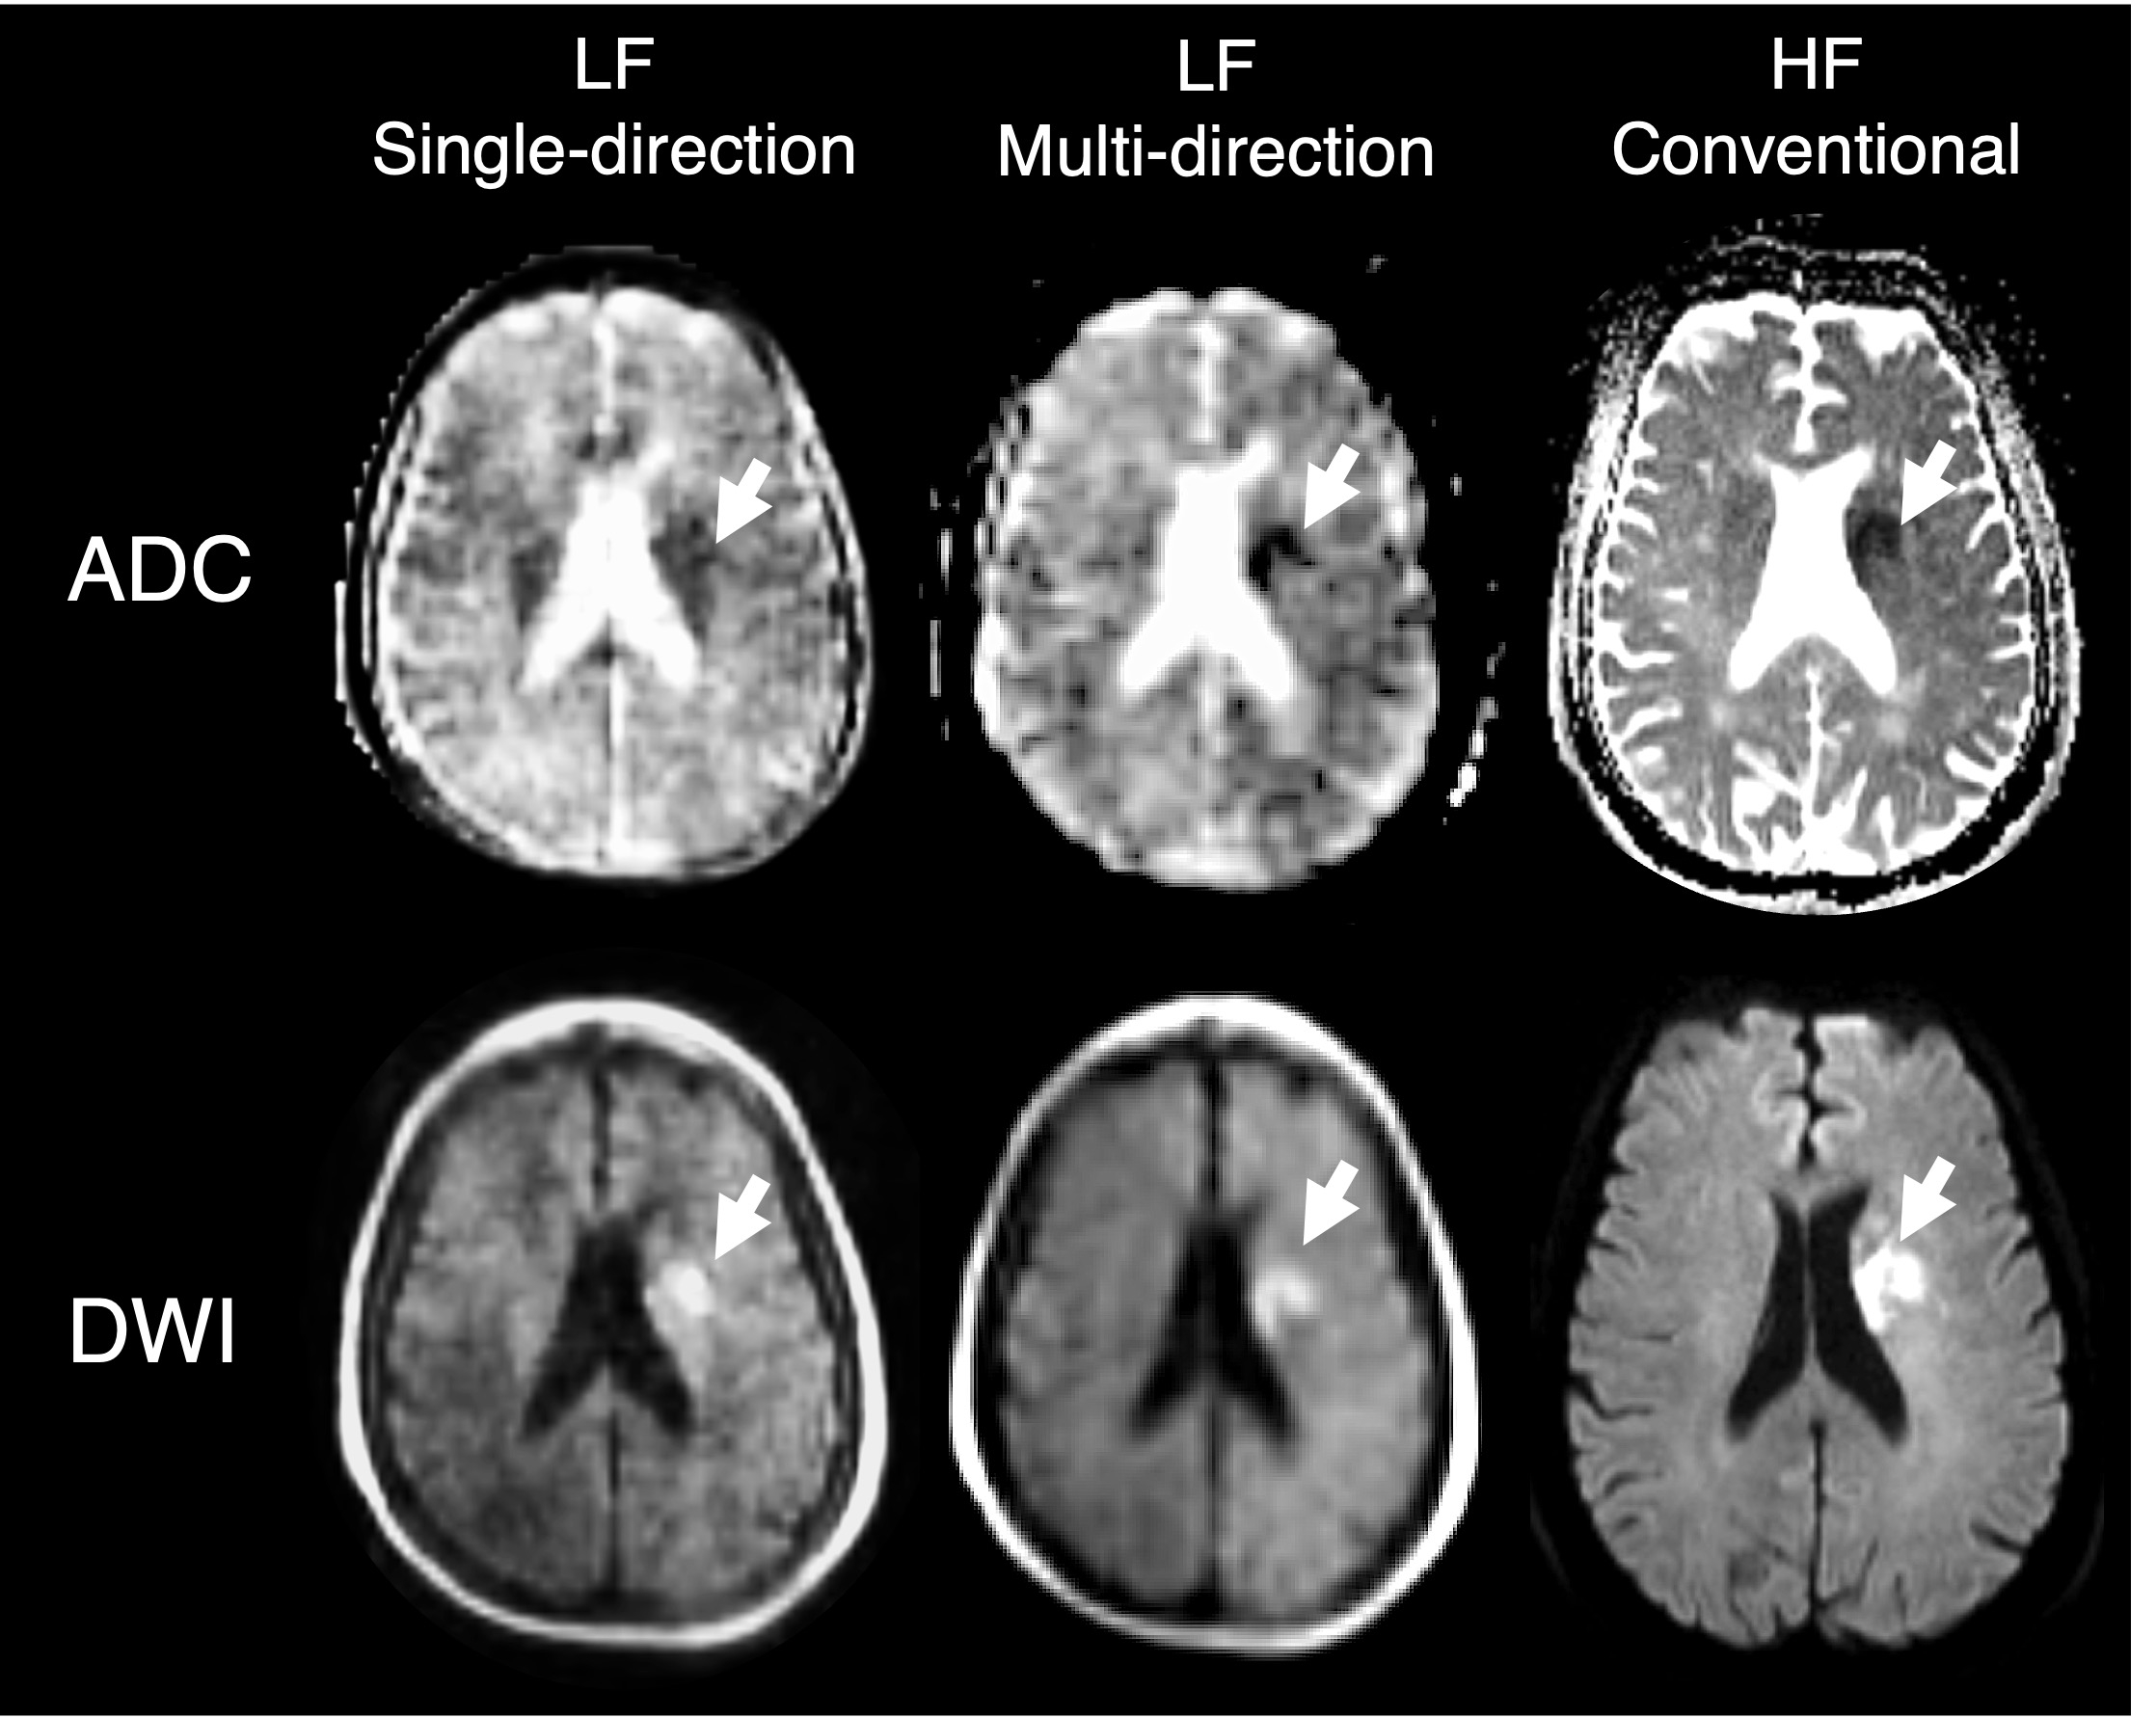

Abstract Body: Introduction: Portable, low-field (LF) magnetic resonance imaging (MRI) has the potential to improve access to brain imaging and facilitate diagnosis of acute ischemic stroke (AIS). However, due to longer acquisition time, diffusion-weighted imaging (DWI) at LF is often restricted to a single diffusion direction, which may reduce sensitivity of detection. We developed a multi-direction DWI sequence and evaluated its ability to detect stroke lesions compared with a single-direction sequence.

Methods: Patients with a suspected diagnosis of AIS were prospectively enrolled at three US centers and underwent single-direction b0 and b900 s/mm2 DWI and generation of corresponding apparent diffusion coefficient (ADC) maps on a 0.064 T MRI (Hyperfine Inc.). A subset of patients underwent additional multi-direction DWI (3 diffusion directions in x, y, and z planes) and generation of trace and ADC maps. Two independent assessors evaluated DWI and ADC scans and recorded the presence or absence of stroke lesions and their location (left/right hemisphere). The agreement, positive predictive value (PPV), negative predictive value (NPV), sensitivity, and specificity were calculated for both single- and multi-directional images as compared to the ground-truth clinical diagnosis.

Results: A total of N=66 patients were included, with N=18 undergoing additional multi-directional acquisition. Of these patients, N=36 had a confirmed ischemic stroke, and N=29 had a stroke mimic with no evidence of infarction or diffusion restriction abnormality on conventional high-field imaging. Agreement between assessors regarding lesion detection on single-direction DWI was κ=0.88 and κ=0.84 on ADC, with a κ=0.92 agreement on lesion location. On multi-directional LF-MRI, agreement increased to κ=1.0 for DWI, ADC, and lesion location. Predictive values for detecting AIS on single-direction DWI revealed a PPV of 83.9% and NPV of 71.4% which was associated with a 72.2% sensitivity and 83.3% specificity. NPV, PPV, sensitivity and specificity all increased to 100% when multi-directional DWI was assessed.

Conclusion: LF single-direction diffusion is sensitive and specific for the detection of acute ischemic infarcts, except for small lesions residing in white matter tracts that align with diffusion gradient direction. A novel LF multi-directional DWI sequence can overcome this limitation and potentially improve qualitative lesion conspicuity. Validation in a larger cohort is warranted.